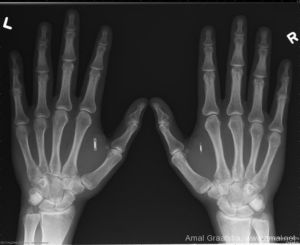

unnamed-file

Puces RFID implantées dans les mains.